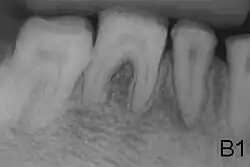

- Enamel of abnormal thickness due to malfunction in enamel matrix formation. Enamel is very thin but hard & translucent, and may have random pits & grooves. Condition is of autosomal dominant, autosomal recessive, or x-linked pattern. Enamel differs in appearance from dentine radiographically as normal functional enamel.[20]

- Enamel defect due to malfunction of enamel calcification, therefore enamel is of normal thickness but is extremely brittle, with an opaque/chalky presentation. Teeth are prone to staining and rapid wear, exposing dentine. Condition is of autosomal dominant and autosomal recessive pattern. Enamel appears less radioopaque compared to dentine on radiographs.